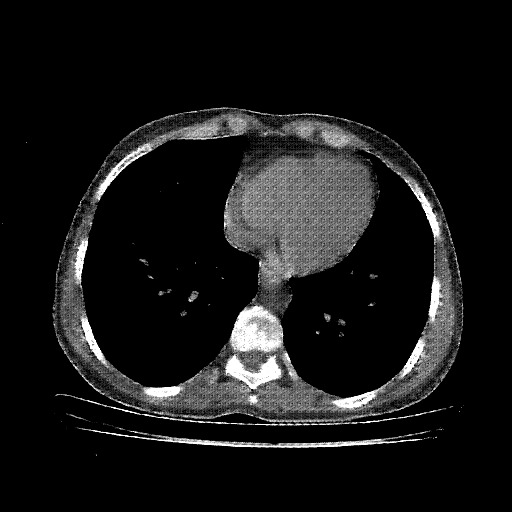

Reconstructed NATIVE CT scan (cycle consistency)

Full window (WL 1023.5, WW 4095 β†’ Low βˆ’1024, High +3071)

Lung window (WL -600, WW 1500 β†’ Low βˆ’1350, High +150)

Mediastinum window (WL 40, WW 400 β†’ Low βˆ’160, High +240)